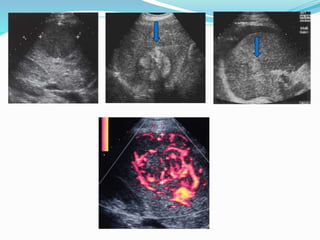

•Ecografía

•Ecografía con contraste

Ecografía

Sens.

>5 cm 75 % Esp.:93 %

3-5 cm 50 % VPP:14 %

2-3 cm 20 % ND: 4,6 %

1-2 cm 13 %

Única técnica en tumores avanzados

Mejora con potenciadores de señal (contrastes)

Técnica dependiente de explorador

Situaciones especiales: atrofia hepática, obesidad,

esteatosis, lesiones isoecogénicas, subdiafragmáticas,...

Hepatocarcinoma Ecografía Sens. >5 cm 75% Esp.:93 % 3-5 cm 50 % VPP:14 % 2-3 cm 20 % ND: 4,6 % 1-2 cm 13 % Única técnica en tumores avanzados Mejora con potenciadores de señal (contrastes) Técnica dependiente de explorador Situaciones especiales: atrofia hepática, obesidad, esteatosis, lesiones isoecogénicas, subdiafragmáticas,...